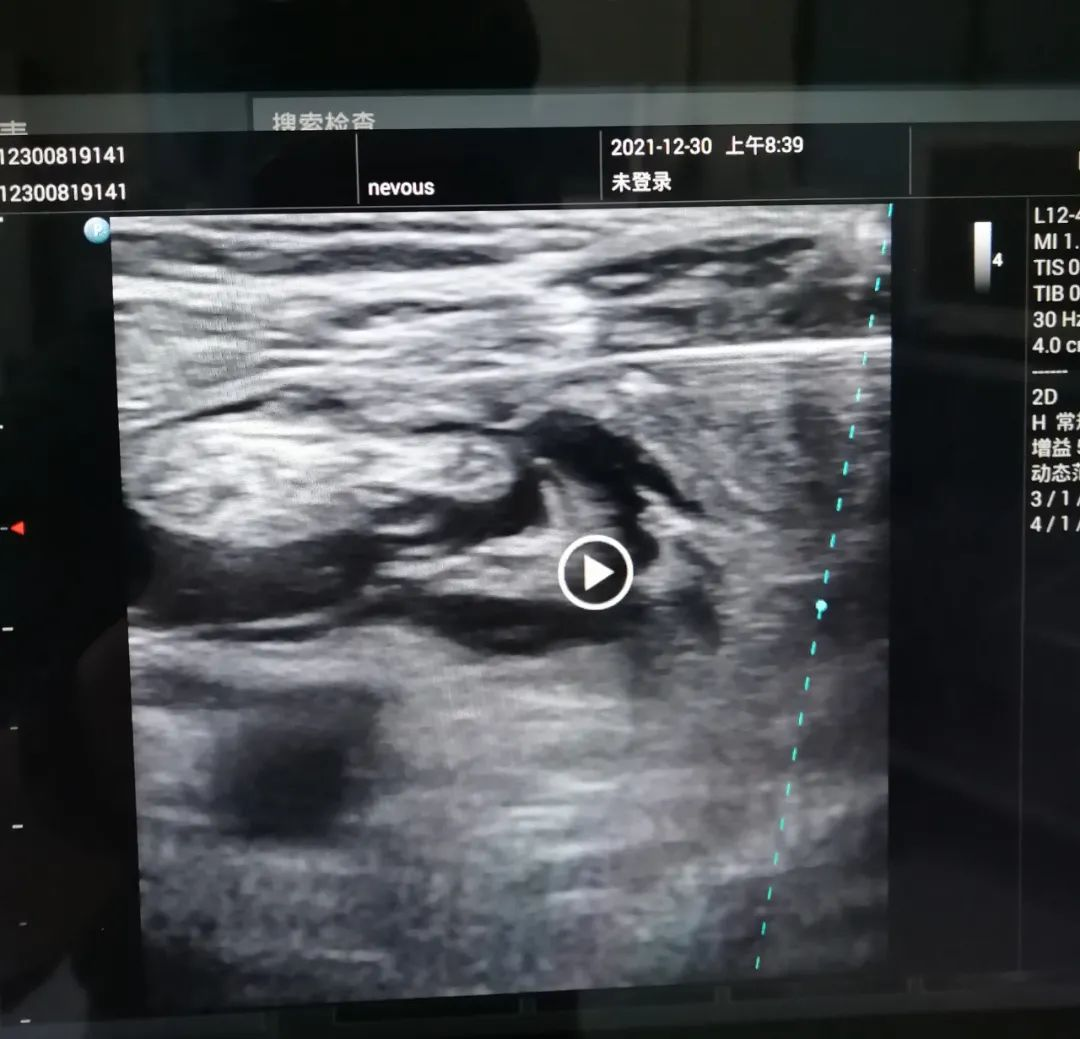

B超引导下坐骨神经阻滞

坐骨神经实际上是由腓总神经和胫神经组成;这两根神经自起始部至腘窝以上,由结缔组织总鞘将其包绕于内,但两神经的纤维并不是交叉连接在一起,坐骨神经大多数经梨状肌下孔出骨盆至臀部。继而向外下经大转子与坐骨结节之间垂直下行至股后部。并从骨盆下行至腘窝,直到腘区彼此分开,胫神经从内侧通过,腓总神经从外侧通过。胫神经支配小腿后侧屈肌群和足底感觉;腓总神经支配小腿前肌群和足背肌,支配足背及趾背大部分皮肤。